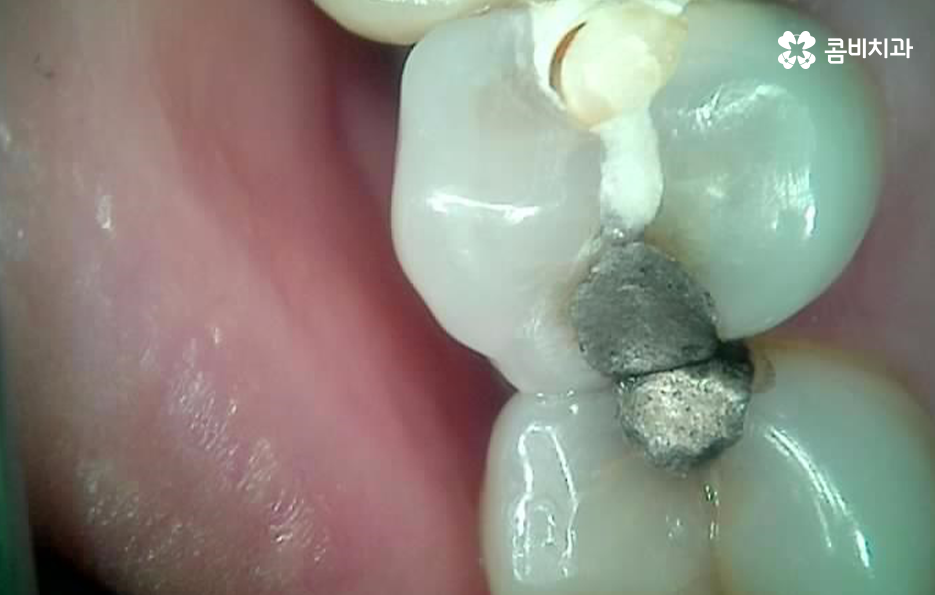

누구나 살다보면 치아에 충치부터 작은 깨짐 등으로 인해 요즘은 대부분 레진이지만 과거에는 아말감과 같은 치료를 해본 분들이 많을텐데 이러한 치과 보철치료를 받았던 분들이 시간이 지나면서 보철물 안으로 2차충치가 발생해서 고생하는 사례가 많이 있어요

많은 환자분들께서 이미 충치 치료를 했던 부위인데 왜 또 충치가 생길 수 있는지 의아해 하시는 분들도 계실 거예요. 충치 치료를 했던 부위를 살펴보면 보철 재료와 치아 사이에 경계면이 있다는 것을 알 수 있는데요.

충치 치료 후에는 보철물과 치아 사이의 경계선 부분에서 보철물의 접착제가 녹는 경우도 있고 보철물 자체의 손상이 발생되는 경우도 있으며 보철물은 멀쩡하더라도 자연치아가 마모되고 깨지는 등의 문제가 발생될 수 있는데 이때 보철물과 치아 사이에 틈이 발생되면 치아 내부로 세균이 침투하여 2차충치가 발생되는 원리라고 할 수 있어요